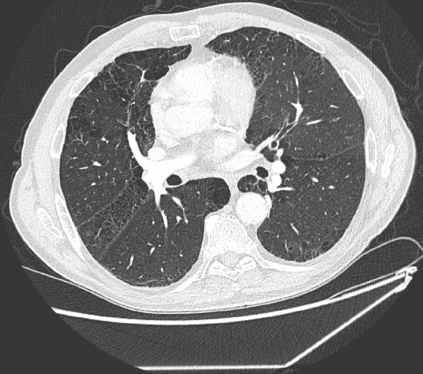

The COVID-19 pandemic has had a considerable impact on day-to-day life. Tackling the disease by providing the necessary resources to the affected is of paramount importance. However, estimation of the required resources is not a trivial task given the number of factors which determine the requirement. This issue can be addressed by predicting the probability that an infected patient requires Intensive Care Unit (ICU) support and the importance of each of the factors that influence it. Moreover, to assist the doctors in determining the patients at high risk of fatality, the probability of death is also calculated. For determining both the patient outcomes (ICU admission and death), a novel methodology is proposed by combining multi-modal features, extracted from Computed Tomography (CT) scans and Electronic Health Record (EHR) data. Deep learning models are leveraged to extract quantitative features from CT scans. These features combined with those directly read from the EHR database are fed into machine learning models to eventually output the probabilities of patient outcomes. This work demonstrates both the ability to apply a broad set of deep learning methods for general quantification of Chest CT scans and the ability to link these quantitative metrics to patient outcomes. The effectiveness of the proposed method is shown by testing it on an internally curated dataset, achieving a mean area under Receiver operating characteristic curve (AUC) of 0.77 on ICU admission prediction and a mean AUC of 0.73 on death prediction using the best performing classifiers.